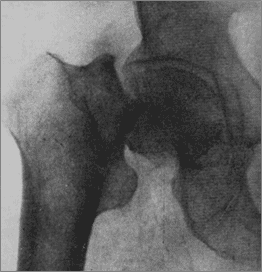

Поперечный субкапитальний перелом шейки бедренной кости